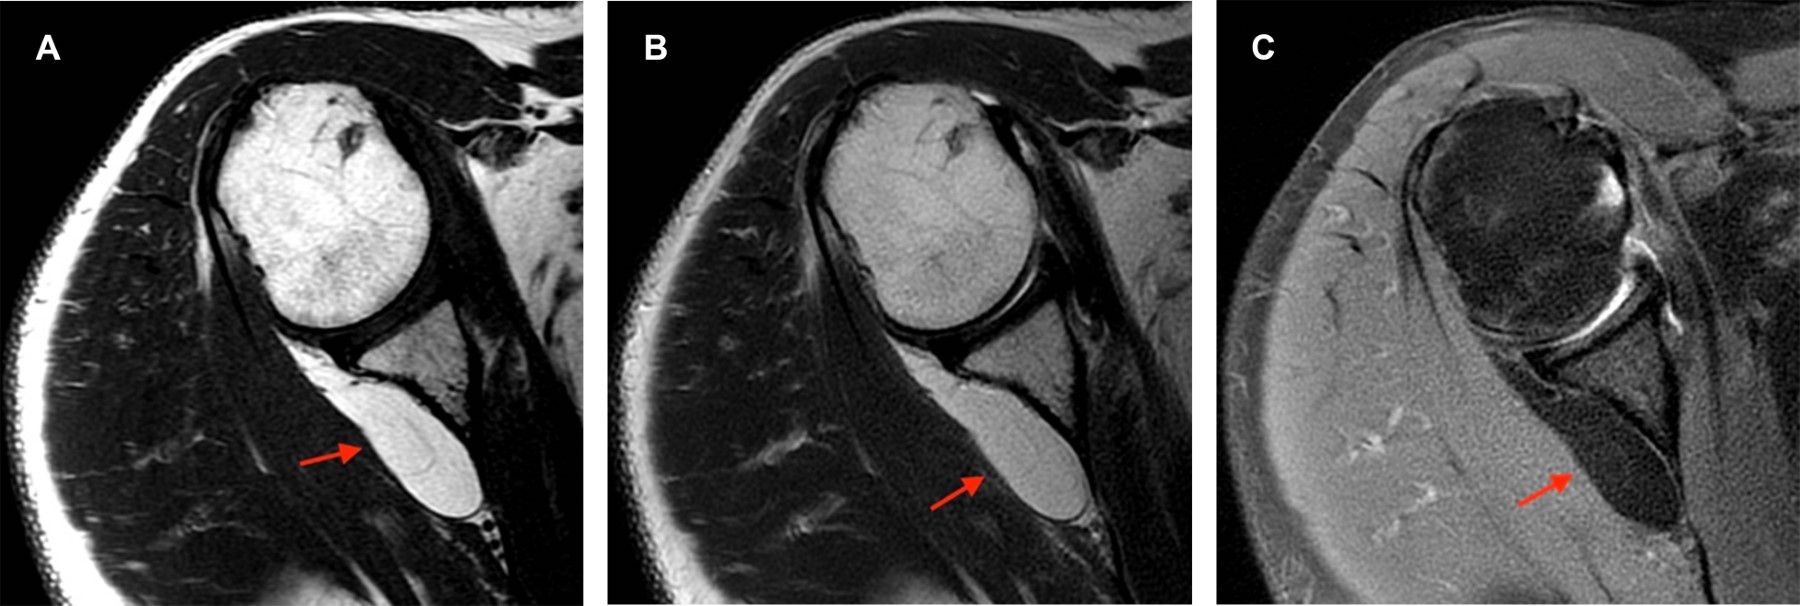

En el estudio de resonancia magnética entre fibras musculares del infraespinoso se observa imagen ovoidea, de márgenes bien delimitados, isointensa al tejido graso en secuencias T1, T2 y densidad protónica con saturación grasa, con diámetros aproximados en plano axial de 5.5 × 1.3 cm, en plano sagital de 3.1 × 1.4 cm y en coronal de 3.8 × 2.9 cm, con imágenes lineales internas hipointensas en todas las secuencias menores de 2 mm (Figura 1). La lesión se extiende por toda la fosa infraespinosa con involucro de algunas fibras musculares del redondo menor y desplaza levemente el infraespinoso (Figura 2).

La resonancia magnética es el estudio de imagen óptimo para valoración de lesiones lipomatosas de localización profunda.1 Se valora el tamaño y morfología, homogeneidad, márgenes, si es uni o multinodular, presencia o ausencia de estructuras lineales y su grosor (delgados < 2 mm, gruesos > 2 mm).5 Su morfología puede ser redonda, oval, fusiforme, irregular poligonal o en forma de pesa y usualmente no encapsulados.3 Caracterización tisular: tienen alta intensidad de señal en T1 y T2 y suprimen similar a la grasa en secuencias de supresión grasa. Los intramusculares contienen fibras musculares entremezcladas, isointensas al músculo normal en T1 y T2. Estas interdigitaciones muestran una apariencia estriada patognomónica de estos lipomas.3